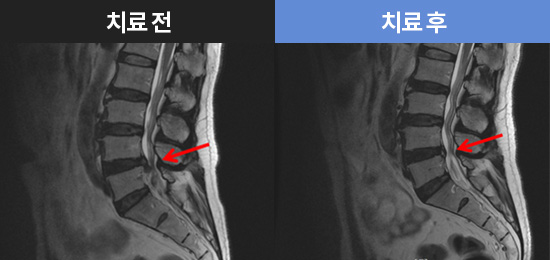

CHAMJALHAM MRI로 보는 치료결과